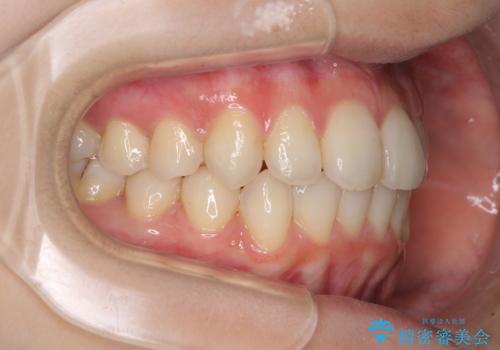

- 前歯のデコボコを気にして来院された患者様です。

叢生と捻転が随所に認められるものの、マウスピースで十分対応可能であったため、インビザラインにて矯正治療を行うこととしました。